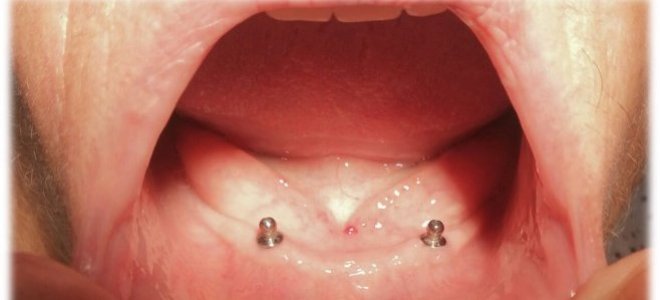

Muchos hombres y mujeres, que se encuentran con su maxilar inferior sin dientes, utilizan prótesis dentales con muy malos resultados debido a que sus condiciones anatómicas impiden que este aparato se retenga adecuadamente. Esta situación causa que las personas se aíslen socialmente, perdiendo su calidad de vida social y personal.

Hernán Cifuentes, Jefe del Departamento de Salud Oral del SSVQ, explicó que “el Ministerio de Salud destinó 50 millones para concretar, a través de las municipalidades, un plan especial de implantes. “Una de las condiciones es que los establecimientos de salud contaran con pabellones de cirugía menor para instalar los implantes a pacientes desdentados totales inferiores y que portaran prótesis regularmente”.

El odontólogo señaló que más de 30 personas ya se encuentran con sus implantes instalados y terminados, “y dentro de los próximos meses deberíamos terminar el proceso y llegar a los 300 beneficiados.  El efecto que tienen estos implantes desde el punto de vista social es muy importante, ya que estos pacientes no pueden portar sus prótesis por su condición anatómica y generalmente desaparecen de la vida social, se esconden de la familia y se aíslan de sus amigos. Estos implantes inferiores vienen al rescate de estos pacientes y lograr insertarlos nuevamente en la vida regular”.